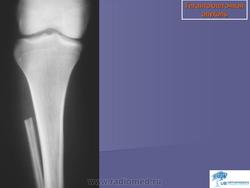

Гигантоклеточная опухоль.

Случай 8: рентгеновский снимок